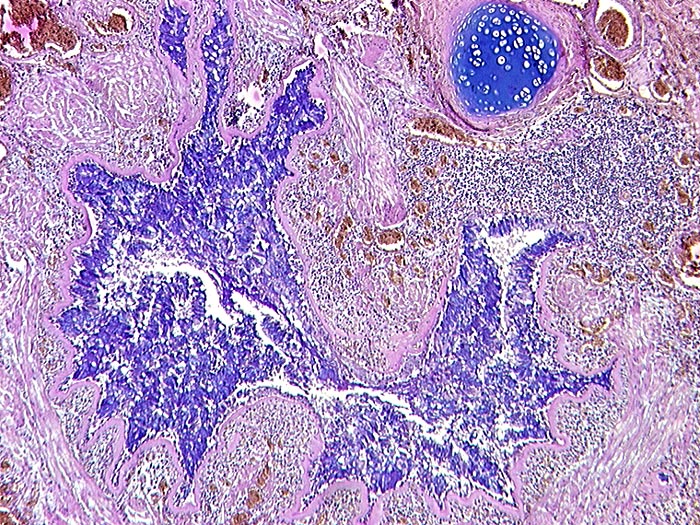

AP/ Asthma bronchiale

Asthma bronchiale

Bronchus

Makroskopie

Pathologischer Befund